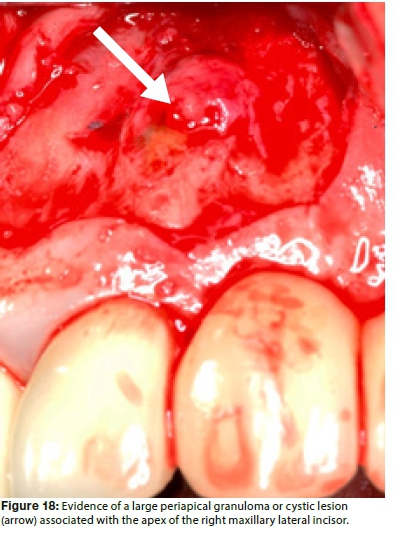

Figure 17 illustrates a periapical radiograph of a failing apicoectomy on a right maxillary lateral incisor of a 45 year old female patient, three years after surgery. The tooth is part of a six-unit fixed bridge. It was evident that an amalgam retrograde was placed, but the surgeon failed to remove all the bacteria from the entire root canal system before placing the retrograde filling material. Several authors have confirmed that if the root canal space is not completely instrumented or inadequately treated, the outcome will be poor.34,35 After anaesthesia, a submarginal flap was designed and the flap reflected using a micro-scalpel and micro-surgical elevators, under 10X magnification. Figure 18 depicts the clinical view after atraumatic reflection of the flap and clearly shows evidence of a large periapical granuloma or cystic lesion associated with the apex of the tooth. mented or inadequately treated, the outcome will be poor.34,35